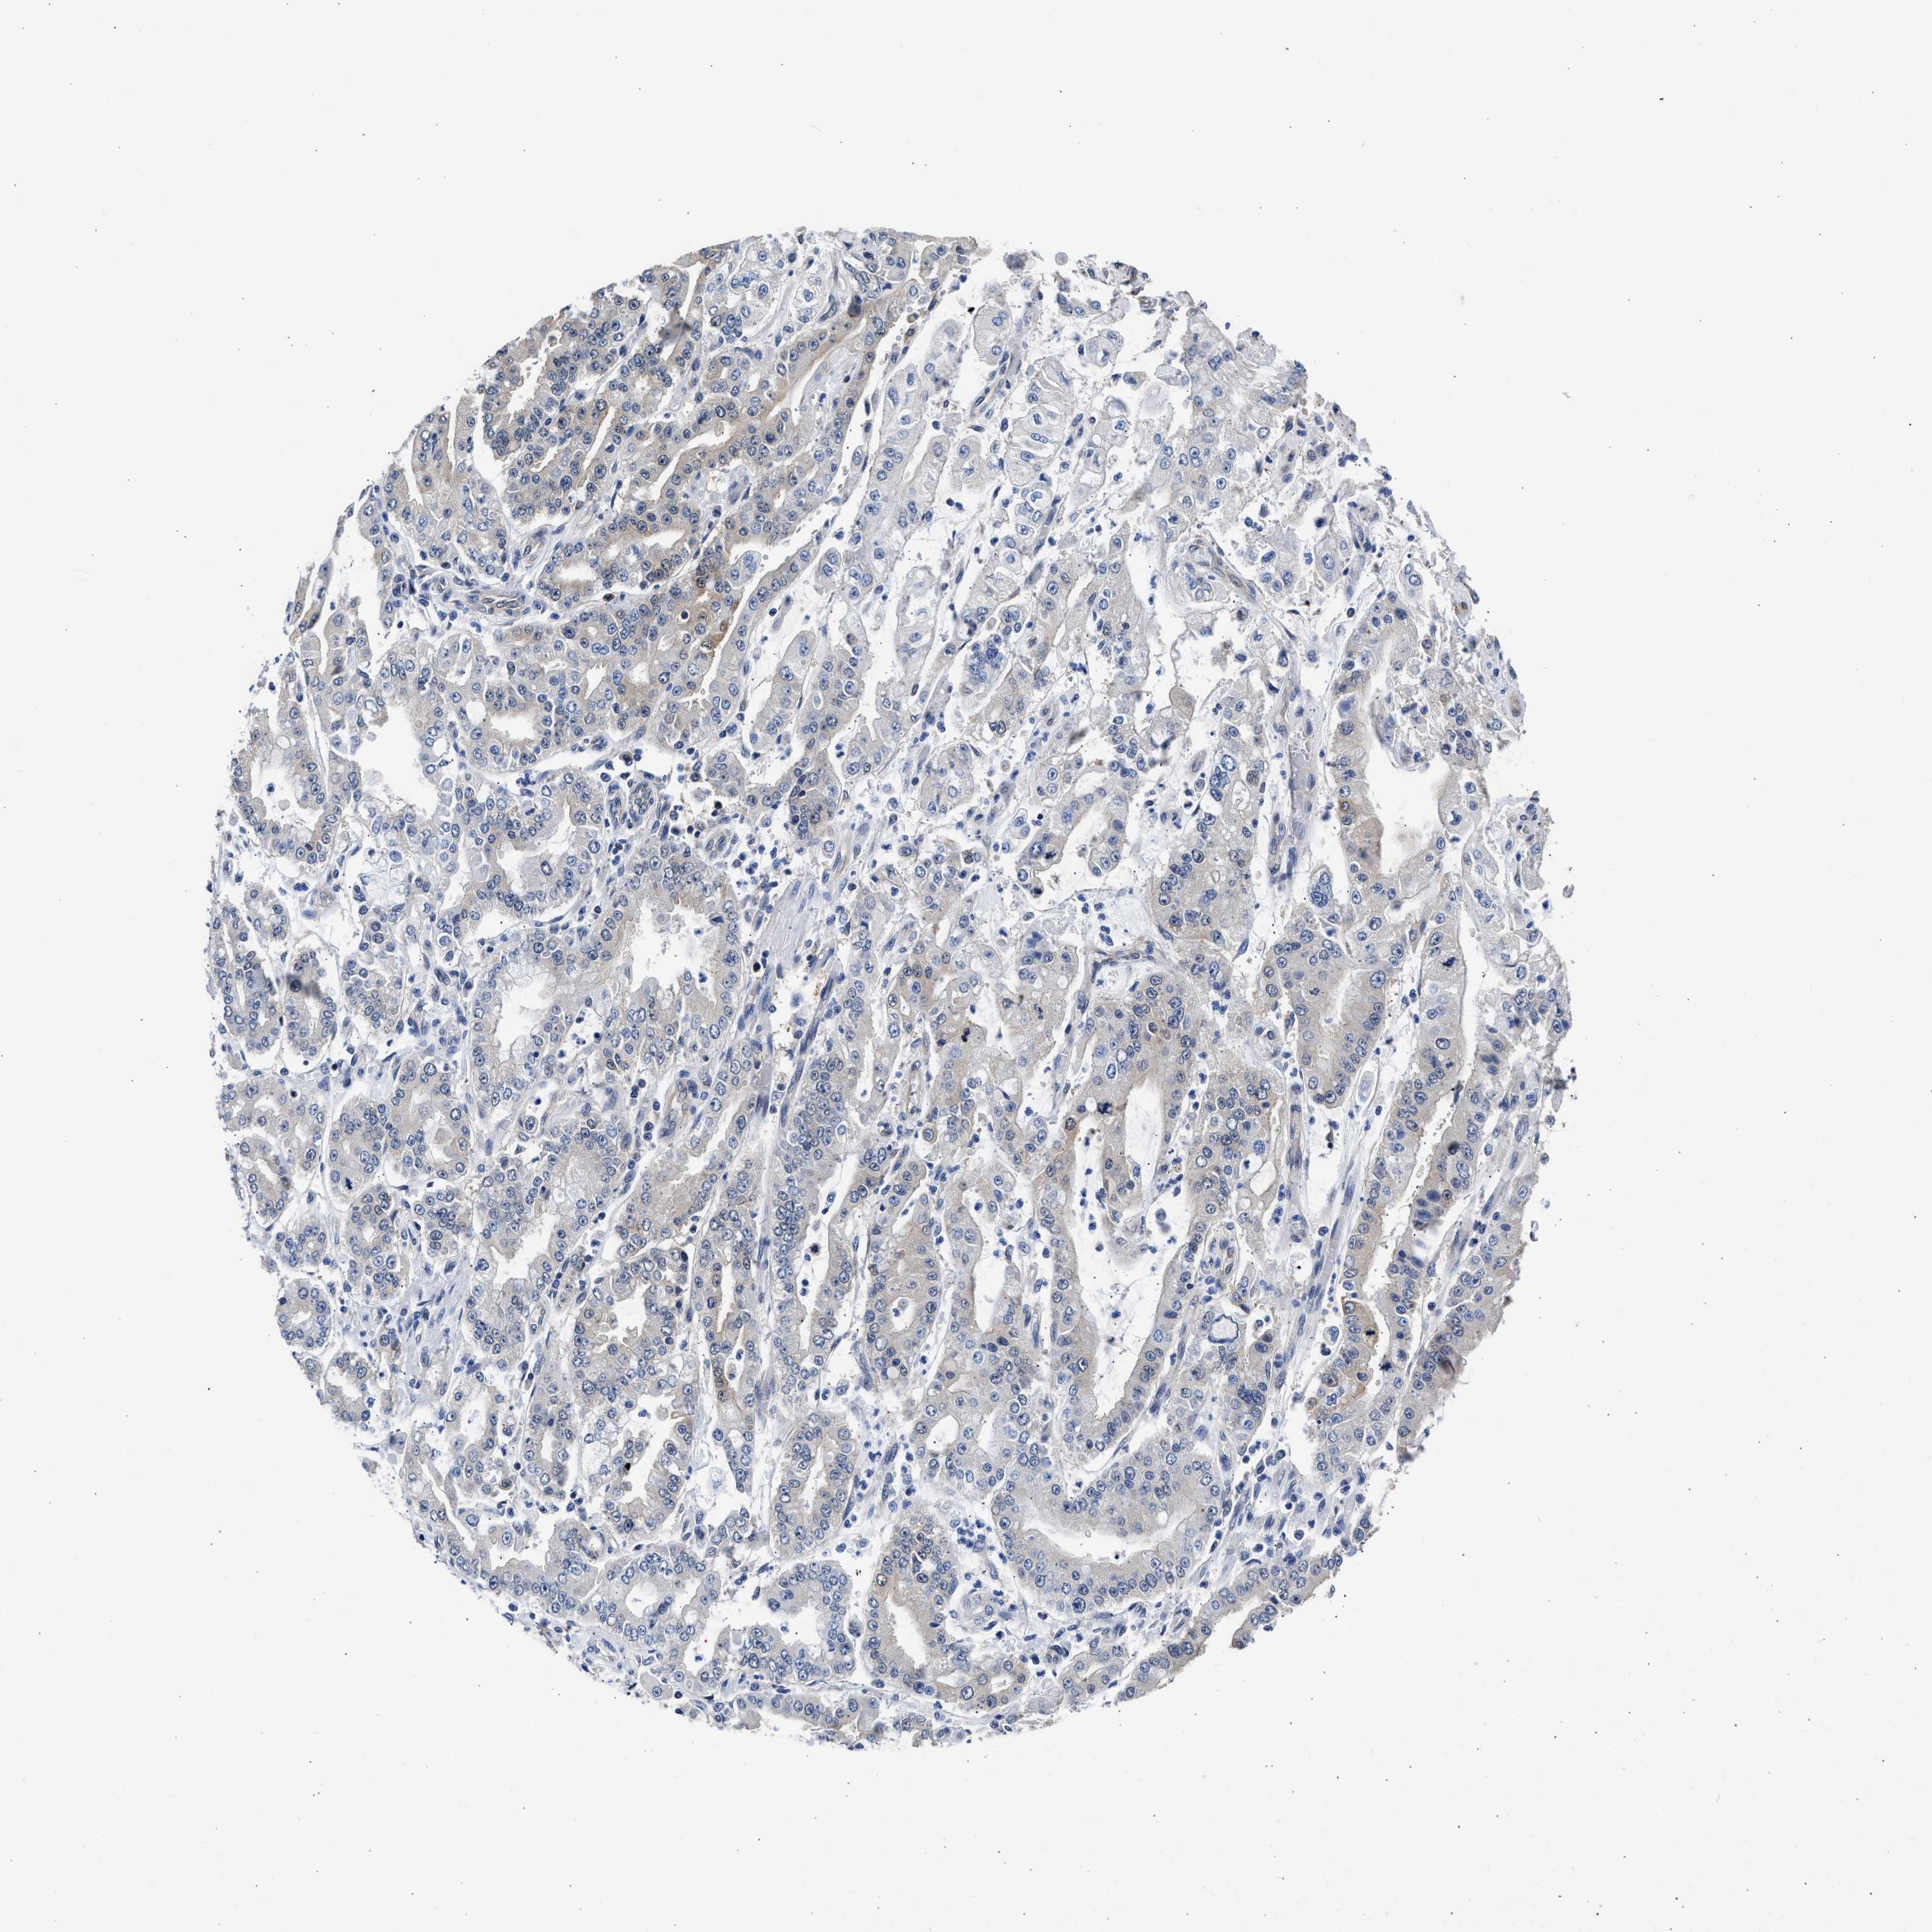

STOMACH CANCER - Protein expressioni

A mouse-over function shows sample information and annotation data. Click on an image to view it in a full screen mode. Samples can be filtered based on level of antibody staining by selecting one or several of the following categories: high, medium, low and not detected. The assay and annotation is described here.

Note that samples used for immunohistochemistry by the Human Protein Atlas do not correspond to samples in the TCGA dataset.

Antibody stainingi

Antibody staining in the annotated cell types in the current human tissue is reported as not detected, low, medium, or high, based on conventional immunohistochemistry profiling in selected tissues. This score is based on the combination of the staining intensity and fraction of stained cells.

Each image is clickable and will lead to virtual microscopy that enables deeper exploration of all samples and also displays staining intensity scores, fraction scores and subcellular localization as well as patient and tissue information for each sample.

Antibody HPA018402

Antibody HPA023959

Staining

High

Medium

Low

Not detected

Intensity

Strong

Moderate

Weak

Negative

Quantity

>75%

75%-25%

<25%

None

Location

Nuclear

Cytoplasmic/membranous

Cytoplasmic/membranous,nuclear

Adenocarcinoma, NOS